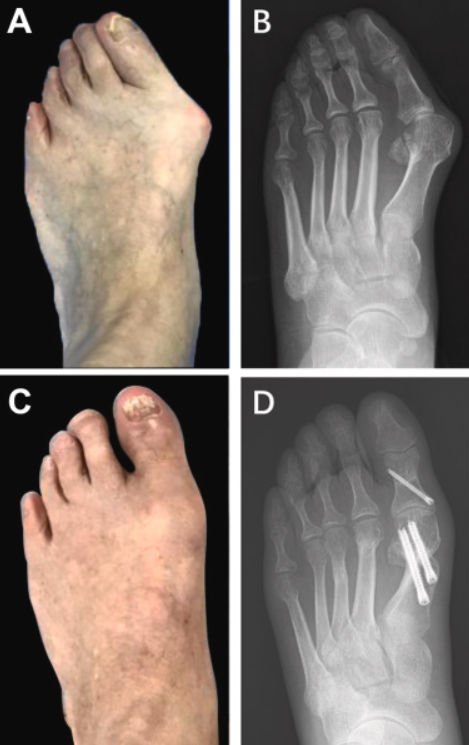

⚫ 수술적 치료

적용 대상:비수술적 치료에도 불구하고 통증이 지속되거나, 변형이 심해 일상생활에 불편을 초래하는 경우

주요 수술 방법:

♦ 뼈 절골술(뼈 자르기 및 배열 교정): 변형된 뼈를 잘라내거나 교정하여 엄지발가락을 바른 위치로 재정렬합니다.

♦ 연부 조직 교정술: 엄지발가락 주위의 인대, 힘줄 등 연부 조직을 조절해 균형을 맞춥니다.

(보통 뼈 절골술시 같이 시행함)